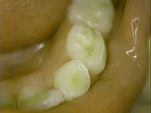

يعرف تآكل الأسنان بالفقدان السطحي للأنسجة السنية الصلبة لأسباب غير التسوس والرضوض التي تؤدي إلى إنكسار جزء من السن، ويعتبر نتيجة طبيعية للتقدم بالعمر، وكنتيجة لهذا التآكل فإن الأسنان سوف تفقد مظهرها ووظيفتها بالإضافة إلى فقدان طبقة الميناء وانكشاف طبقة العاج مما يجعل الأسنان أكثر حساسية. وقد يتطور الأمر إلى التهاب لب السن وموت اللب السني. وينقسم تآكل الأسنان إلى الأنواع التالية، والتي كثيرا ما تتواجد مجتمعة.

1- الإحتكاك Attrition: يؤثر على الأسطح الطاحنة و الحدود القاطعة للأسنان نتيجة الاحتكاك بين الأسنان المتقابلة مثل: صرير الأسنان – العادات الفموية الضارة.

2- السحل Abrasion: يؤثر على منطقة الأعناق للأسطح الخدية للأسنان الأمامية والخلفية وهذا النوع من التآكل الميكانيكي يحدث بسبب عوامل خارجية مثل:

• – معاجين الأسنان التي تحتوي على مواد ساحلة

• – فراشي الأسنان ذوات الأشعار الصلبة

• – عادات خاطئة (تدخين الغليون، عض الأسلاك والخيوط)apresion03.jpg